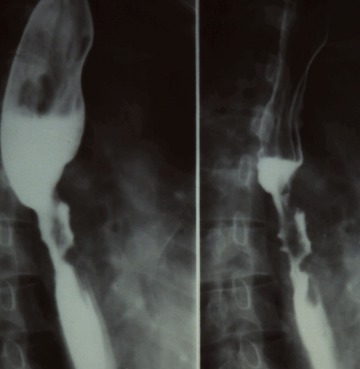

한마디로 딱 구분하자면 위내시경 검사는 카메라를 입으로 넣어 식도를 지나 위와 십이지장 그리고 소장의 시작부분까지는 볼 수 있는 검사방법입니다.

위조영술 검사는 바륨이라는 하얀 액체를 마시고 그 액체가 식도를 타고 내려가면서 위에 쌓였을 때 몸을 이리저리 뒤집어가면서 그 흑백화면을 보면서 읽어내는 검사방법입니다.

바륨현탁액, 요오드제제를 이용해 위의 이상 유무를 검사합니다. 이 용액은 X선 투과가 잘 안되는 물질로 이 용액을 마시고 X선이 발생되는 기계 위에서 몸을 이리저리 돌려가면서 검사를 받습니다. 기계가 알아서 돌아가는 것이 아니라 사람이 직접 그 기계 위해서 몸을 움직여 줘야 합니다.

X선이 발생하는 기계 위에 있으므로 그 방사선이 몸을 투과하므로 미량의 방사선 피폭이 있다는 것은 인지해야 합니다. 위조영술 검사방법은 위를 풍선처럼 팽창시켜 위벽에 조영제 코팅해 위벽 병변 유무를 검사하는 방법과 위가 팽창하지 않은 상태에서 위를 조영제로 채워 검사하는 두가지 방법이 있으며 일반적으로 두가지 다 시행해야 위벽과 안을 다 검사 할 수 있습니다.